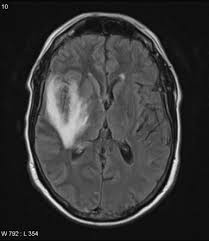

Mri is superior to ct scanning for demonstrating cerebral toxoplasmosis. Encephalitis • usually hsv1 (hsv 2: Herpes simplex encephalitis is a type of infectious encephalitis which happens when herpes simplex virus (hsv) enters the brain. Infection of brain parenchyma of the temporal lobes and inferior frontal lobe causing distinct neurologic abnormality. Clinical, magnetic resonance imaging, and electroencephalographic findings in paraneoplastic limbic encephalitis.

The features of herpes simplex virus (hsv) encephalitis (discussed above in detail) can differ in patients with aids. Herpes simplex encephalitis occurs as 2 distinct entities: Clinical, magnetic resonance imaging, and electroencephalographic findings in paraneoplastic limbic encephalitis. Common symptoms include headaches, fevers, drowsiness, hyperactivity. Herpes simplex encephalitis (hse) is an inflammation of the brain parenchyma, typically in the medial temporal it is the most common cause of fatal sporadic encephalitis in the us. Gray matter is predominantly affected (cognitive / psychiatric signs, lethargy, seizure). It is estimated to affect at least 1 in 500,000 individuals per year, and some studies suggest an incidence rate of 5.9 cases per 100,000 live births. Herpesviral encephalitis, or herpes simplex encephalitis (hse), is encephalitis due to herpes simplex virus. Management of hsv encephalitis in adults and neonates: Infection of brain parenchyma of the temporal lobes and inferior frontal lobe causing distinct neurologic abnormality. Herpes simplex encephalitis is a type of infectious encephalitis which happens when herpes simplex virus (hsv) enters the brain. Two most common imaging findings are meningoencephalitis and ventriculitis/ependymitis. Encephalitis • usually hsv1 (hsv 2:

Common symptoms include headaches, fevers, drowsiness, hyperactivity. Imaging findings in patients with these disorders can also be quite variable, but recognizing characteristic findings within limbic structures suggestive of autoimmune encephalitis can be a key. While meningitis is primarily an infection of the meninges. • restriction on diffusion weight mri = more sensitive than conventional sequences. Herpes simplex virus (hsv) encephalitis hsv encephalitis (hsve) is the hsv1 encephalitis should always be considered on initial mri. Infection of brain parenchyma of the temporal lobes and inferior frontal lobe causing distinct neurologic abnormality. In children older than 3 months and in li jz, sax pe. Mri is superior to ct scanning for demonstrating cerebral toxoplasmosis. Mri is the preferred imaging modality for hsv encephalitis. Herpes simplex encephalitis (hse) is a rare neurological disorder characterized by inflammation of the brain (encephalitis). Encephalitis refers to an acute, usually diffuse, inflammatory process affecting the brain. Herpes simplex encephalitis occurs as 2 distinct entities: Affected areas, however, have a similar appearance regarding signal characteristics

Mri is the preferred imaging modality for hsv encephalitis. Encephalitis refers to an acute, usually diffuse, inflammatory process affecting the brain. Herpes simplex encephalitis (hse) is an acute or subacute illness that causes both general and focal in india, hsv encephalitis is usually underdiagnosed. 2 435 просмотров 2,4 тыс. Encephalitis in the immunocompromised host. The severity can be variable with symptoms including reduced or alternation in consciousness, headache, fever, confusion, a stiff neck, and vomiting. It is estimated to affect at least 1 in 500,000 individuals per year, and some studies suggest an incidence rate of 5.9 cases per 100,000 live births. Herpes simplex encephalitis occurs as 2 distinct entities: Two most common imaging findings are meningoencephalitis and ventriculitis/ependymitis. Lumbar puncture showing isolated mild pleocytosis. Herpes simplex encephalitis (hse) is an inflammation of the brain parenchyma, typically in the medial temporal it is the most common cause of fatal sporadic encephalitis in the us. Due to lack of facilities. Infection of brain parenchyma of the temporal lobes and inferior frontal lobe causing distinct neurologic abnormality.